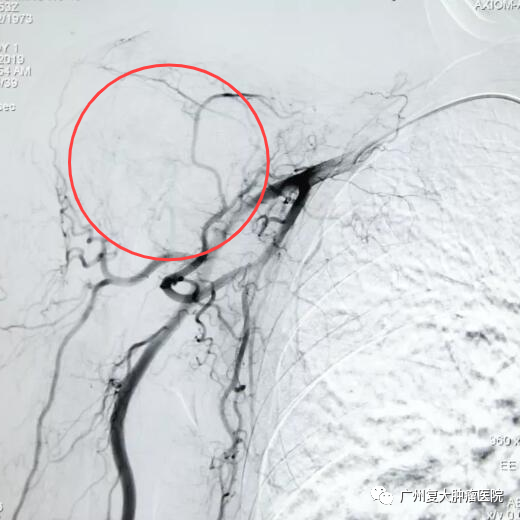

精准介入:DSA+MDCT可以通过将两种二维图像融合成三维图像,全方位了解病灶的血供情况,确保靶病灶得到有效治疗。

不留死角:DSA+MDCT可以通过多个角度了解病灶的血供情况,使每个病灶及病灶的每个部分均得到有效治疗,术后即刻得到影像验证,提供血管内治疗的最佳工作角度,还可以提高工作效率,减少曝光时间。

治疗前

治疗后